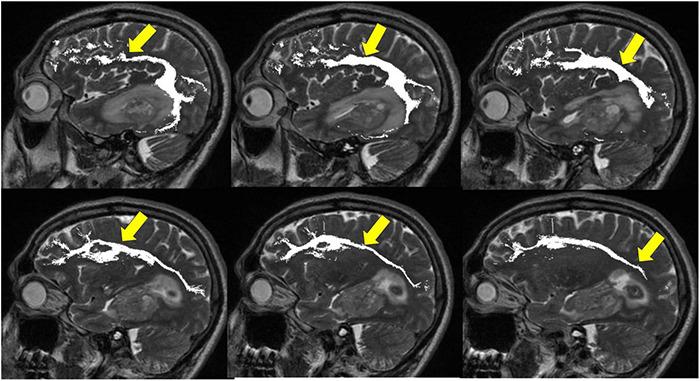

Management of gliomas following initial diagnosis requires thoughtful presurgical planning followed by regular imaging to monitor treatment response and survey for new tumor growth. Traditional MR imaging modalities such as T1 post-contrast and T2-weighted sequences have long been a staple of tumor diagnosis, surgical planning, and post-treatment surveillance. While these sequences remain integral in the management of gliomas, advances in imaging techniques have allowed for a more detailed characterization of tumor characteristics. Advanced MR sequences such as perfusion, diffusion, and susceptibility weighted imaging, as well as PET scans have emerged as valuable tools to inform clinical decision making and provide a non-invasive way to help distinguish between tumor recurrence and pseudoprogression. Furthermore, these advances in imaging have extended to the operating room and assist in making surgical resections safer. Nevertheless, surgery, chemotherapy, and radiation treatment continue to make the interpretation of MR changes difficult for glioma patients. As analytics and machine learning techniques improve, radiomics offers the potential to be more quantitative and personalized in the interpretation of imaging data for gliomas. In this review, we describe the role of these newer imaging modalities during the different stages of management for patients with gliomas, focusing on the pre-operative, post-operative, and surveillance periods. Finally, we discuss radiomics as a means of promoting personalized patient care in the future.

胶质瘤初诊后的管理需要进行周全的术前规划,随后定期进行影像学检查,以监测治疗反应并探查新的肿瘤生长情况。传统的磁共振成像(MR)模式,如T1增强序列和T2加权序列,长期以来一直是肿瘤诊断、手术规划及治疗后监测的主要手段。虽然这些序列在胶质瘤的管理中仍不可或缺,但成像技术的进步使得对肿瘤特征的刻画更加详细。诸如灌注成像、扩散加权成像、磁敏感加权成像等先进的MR序列,以及正电子发射断层显像(PET)扫描,已成为指导临床决策的重要工具,并提供了一种非侵入性方法,有助于区分肿瘤复发和假性进展。此外,这些成像技术的进步已延伸至手术室,有助于使手术切除更安全。尽管如此,手术、化疗和放疗仍使胶质瘤患者的MR图像变化解读变得困难。随着分析和机器学习技术的进步,放射组学在解读胶质瘤成像数据方面具有实现更具定量性和个性化的潜力。在本综述中,我们描述了这些更新的成像模式在胶质瘤患者不同管理阶段的作用,重点关注术前、术后及监测期。最后,我们讨论放射组学作为未来促进个性化患者护理的一种手段。